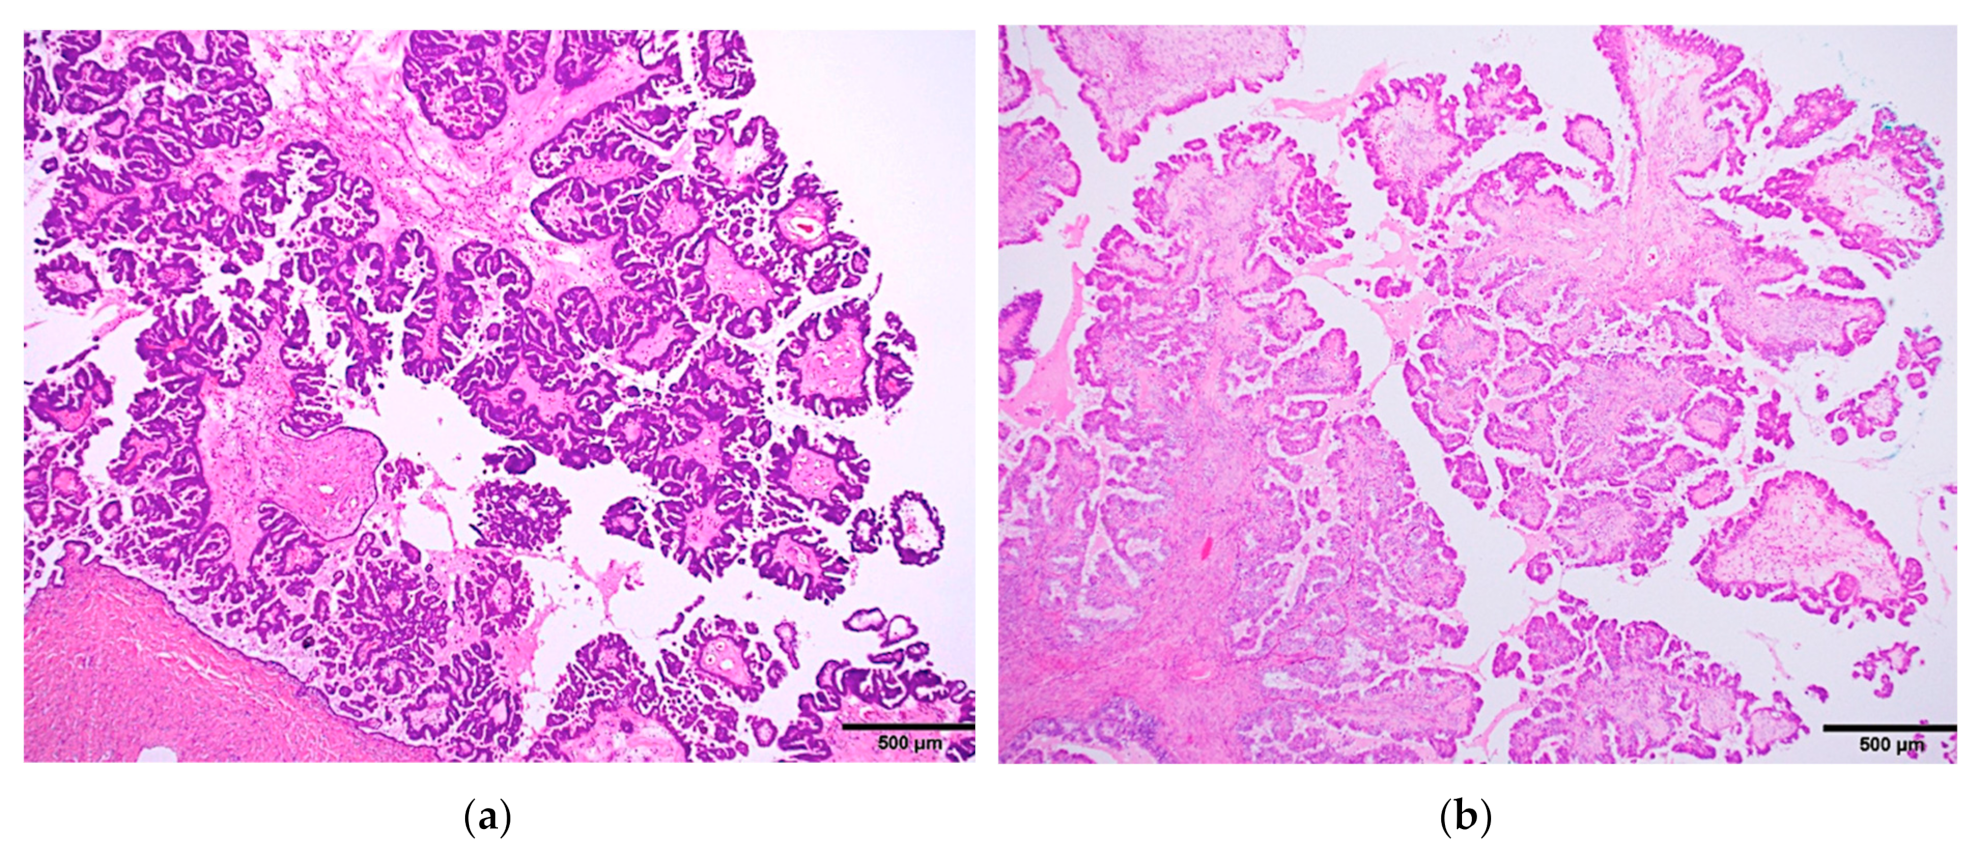

a Picture of an ovarian seromucinous borderline tumour. The

a Picture of an ovarian seromucinous borderline tumour. The capsule is